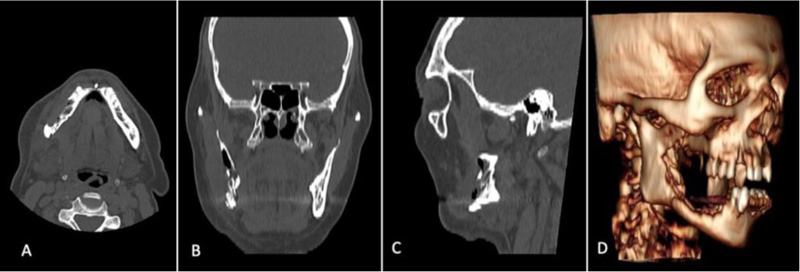

None of the condylar specimens harvested during wide mandibular resection showed any morphologic alteration consistent with necrosis. We report one emblematic case, a Stage III MRONJ of the right mandible, where we performed a right Hemi-mandibulectomy from the horizontal branch of the mandible to the right condyle due to a sub-condylar pathologic fracture (Figs. 3 and 4).

Literature research did not report any case of condylar MRONJ neither as a single site nor as additional localization, and additional analysis on temporomandibular disorders prevalence and epidemiology show how MRONJ was never cited as the cause of disease [22-24]. The sample case we described, where the patient’s disease extended from the right canine to the right subcondylar area, led us to investigate why the MRONJ did not advance further to the condyle and if single site involvement of the condyle ever occurred during our practice (Figs. 1-3). Therefore, we developed two hypotheses that might explain the absence of condylar involvement in MRONJ: the first one was built on the different embryogenetic origin of the condyle compared to the rest of the mandible; the second one was based on the effects of BP and anti-resorptive medications on the different vascular patterns of the mandible components [25, 26].